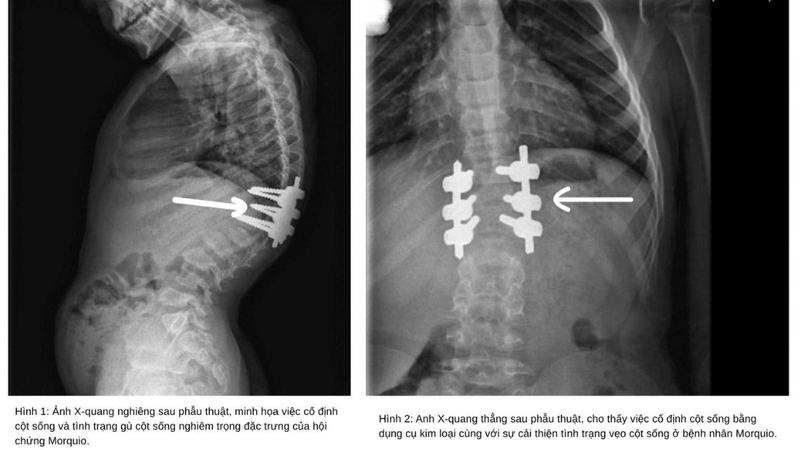

Trong những trường hợp biến dạng nặng, bác sĩ có thể chỉ định phẫu thuật cột sống, thay khớp hoặc các can thiệp chỉnh hình khác nhằm nâng cao khả năng vận động và cải thiện chất lượng sống.